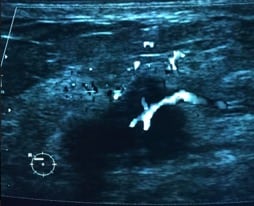

Ultrasonido de mama. El ultrasonido utiliza ondas de sonido para generar imágenes de las estructuras dentro del cuerpo. Se puede utilizar el ultrasonido para determinar si un bulto nuevo en la mama es una masa sólida o un quiste lleno de líquido.

• Cáncer de mama por ultrasonido